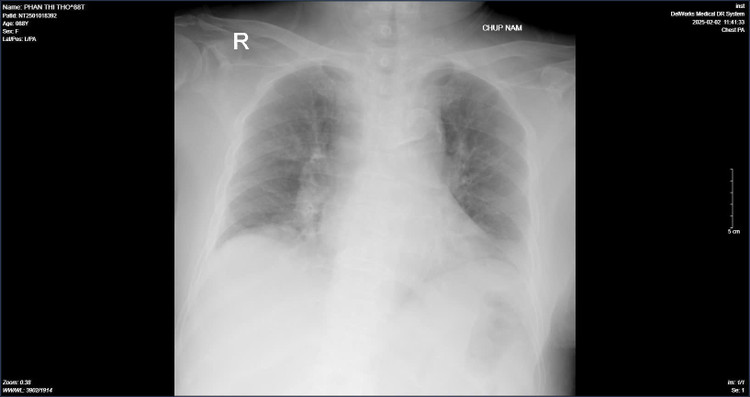

| Hình ảnh chụp phổi của bệnh nhân T. khi vào viện và hình chụp phổi sau quá trình điều trị - Ảnh BVCC |

Theo ghi nhận từ khoa Bệnh nhiệt đới – Bệnh viện Nội tiết Trung ương đang điều trị cho bệnh nhân Phan Thị T. (88 tuổi) mắc virus cúm A. Cách vào viện 2 ngày, bệnh nhân xuất hiện ho khan, sốt 38-39 độ C, đi mua kháng sinh, long đờm uống không đỡ. Cách vào viện 1 ngày bệnh nhân sốt cao, ý thức chậm nên được người nhà đưa vào bệnh viện Nội tiết Trung ương.

Sau khi tiếp nhận thăm thăm khám, bệnh nhân được chẩn đoán: Suy hô hấp, viêm phổi, cúm A- Đợt cấp suy thận mạn; Đái tháo đường typ 2, tăng huyết áp, rối loạn lipid máu, suy tim, bệnh thận mạn giai đoạn 3, biến chứng thần kinh ngoại vi. Bệnh nhân có tiền sử cắt cụt 1/3 cẳng chân trái do bệnh động mạch ngoại biên.

Sau nhập viện, bệnh nhân được điều trị tích cực bằng thuốc kháng virus, kháng sinh, oxy liệu pháp, kiểm soát dịch ra vào, đái tháo đường, tăng huyết áp; Chữa triệu chứng, nâng cao thể trạng, tập phục hồi chức năng. Sau 4 ngày điều trị, bệnh nhân tỉnh, tiếp xúc tốt, cai được oxy, ăn uống bình thường, chức năng tim, chức năng thận cải thiện.